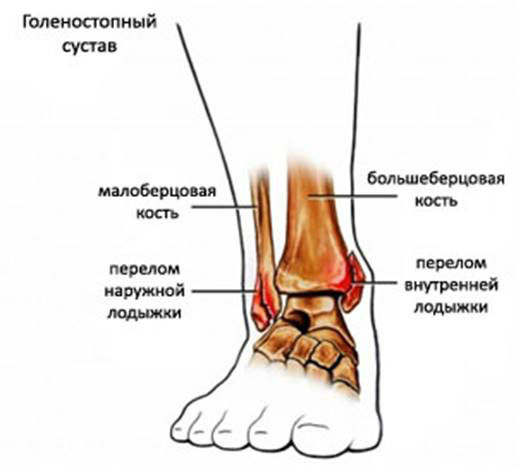

Под лодыжкой, или щиколоткой подразумевают нижнюю выступающую часть голени. Она представляет собой два костных нароста, которые расположены соответственно возле наружной и внутренней части стопы. Медики выделяют два отдела в щиколотке:

- латеральный, наружный – часть малоберцовой кости;

- медиальный, внутренний – отросток большеберцовой кости.

Оба отдела формируют собой вилку голеностопа.

В медицинской практике различают перелом внутренней и наружной лодыжки.

В зависимости от локализации повреждения медики выделяют:

- перелом медиальной лодыжки;

- перелом латеральной.

Перелом наружной лодыжки влечет за собой повреждение малоберцовой кости, в результате которого симптомы травмы могут ощущаться не в полной мере. Объясняется это тем, что эта кость не берет на себя большие нагрузки и крепится к большеберцовой. Наиболее яркий признак в таких случаях – отек голеностопа.

Перелом внутренней лодыжки влечет за собой и нарушение целостности большеберцовой кости. При этом травматологи выделяют: